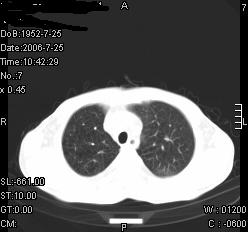

患者,男,54岁,咳嗦,咳痰20天。抗炎治疗2周。现esr76mm/h,目前患者症状明显好转,但发现两次ct片未见明显变化。两次分别做与7.25、7.31。第一次诊断右肺上叶炎症累计胸膜。大家看,从影像上内排除结核吗?

结核的可能性非常大,右上肺病变应该考虑干酪性肺炎。理由:

1.纵隔内多发淋巴结肿大。

2.esr76mm/h。

3.虽经抗炎治疗肺窗病灶有所吸收、减小,但纵隔窗病灶形态、密度、范围无明显变化。如果是单纯的大叶性肺炎,“抗炎治疗2周,目前患者症状明显好转”病灶应该基本消散了,至少也处于吸收消散期,密度变淡、范围变小。同时本病例所示其内的密度不均匀,见多发大小不一空洞样影也不符合大叶性肺炎吸收消散期表现。

病灶特点:片状 索条 结节混杂影,部分融合,密度不均,广泛累及相应胸膜.

临床治疗;二周未吸收.但症状好转.

多考虑:肺结核.